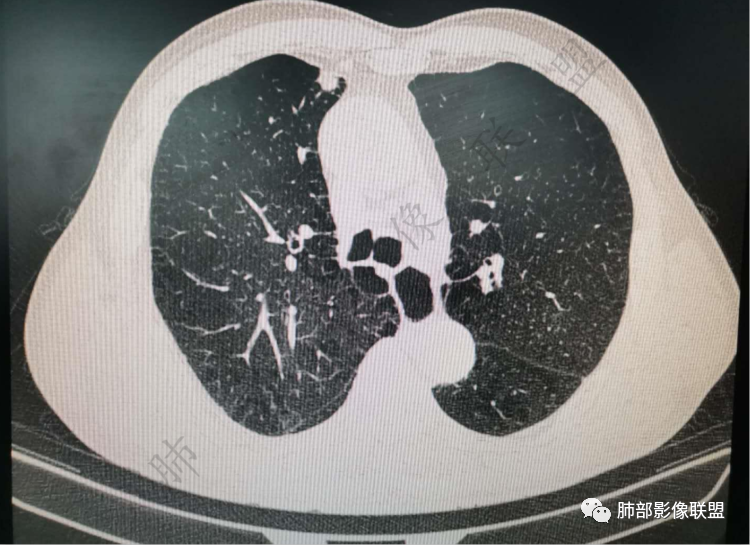

右肺上类圆形叶结节,周边见细软毛刺,增强后呈环形明显强化,内部坏死,邻近胸膜光滑,结合病史2个月明显增大,考虑炎性可能性大。

老年男性,炎性指标略高,肺气肿背景。右肺上叶胸膜下结节,部分边缘平直,部分稍膨隆,供血血管增粗,增强扫描病灶中心密度减低,呈环形强化,邻近脂肪间隙清晰。考虑炎性肉芽肿或慢性炎症,鉴别鳞癌。

右肺上叶前段胸膜下结节,边缘分叶毛刺,血管集束,支气管截断,纵膈胸膜牵拉,内乳动脉增粗,密度不均,中央可见坏死,两个月短期随访结节有增大,考虑恶性,腺癌。鉴别结核。

老年男性,肺气肿背景,右肺上叶胸膜下弧立实性不规则结节,密度不均,其内低密度坏死影,支气管似有截断,血管集束,2月复查明显增大,考虑恶性,鳞癌可能大,鉴别炎性肉芽肿

老年男性,炎性指标略高。影像表现右肺上叶胸膜下结节,膨胀性生长部分边缘平直,边界清晰,病灶可见血管集束征,近段支气管阻断?增强扫描病灶中心密度减低,低密度区边界模糊,外围环形强化。老年性,不能排除恶性病变,周围性鳞癌,其次才考虑炎性肉芽肿或慢性炎症

老年男性,肺气肿背景,右肺上叶前段胸膜下结节,部分边缘毛糙,血管集束增粗,支气管似有截断,胸膜牵拉,结节密度不均,两个月随访结节有增大,考虑恶性,肺癌可能;另右肺上叶后段肋胸膜区小片状类结节影,考虑炎性可能。

右肺上叶前段结节,边缘毛糙,血管进入,局部细支气管似闭塞,增强有强化,中心密度似减低,2月明显增大,肺气肿背景,首先考虑炎性结节,鳞癌增大可以很快,对比老片看看

老年男性,白细胞计数及CRP稍高,右肺上叶结节,两个月来有增大,部分边缘可见边界模糊的GGO,局部边缘平直、凹陷,临近胸膜增厚,内见坏死,坏死区边界未见明显壁结节,壁较厚而且均匀强化,支气管似乎有扩张然后截断,近端血管增粗明显。考虑炎性病变,脓肿?有结核病人密切接触史,注意是否为结核。有点难以理解的是为什么右侧内乳动脉增粗明显。

老年男性,无症状,炎性指标增高。肺气肿背景,右肺上叶前段结节,边缘部分平直部分澎隆,血管集束,支气管至病变边缘似截断,近端扩张。增强环形强化,中心坏死。两月内病灶增长太快,考虑炎性肉芽肿,慢性脓肿?结核?癌待排。

边缘平直

宽基底与胸膜相连,附近胸膜增厚,糊墙

内部有低强化区,边界尚清

还是支持炎性放前面,恶性待排